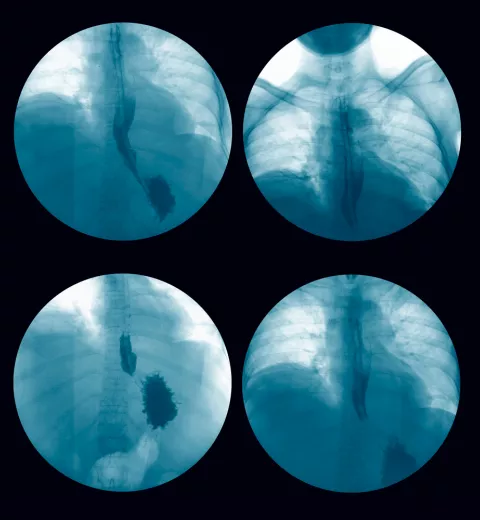

Las vacunas para la diabetes tipo I, la mejora de la imagen endoscópica o los acances en irradiación ultravioleta germicida son algunos de los temas médicos emergentes de 2017